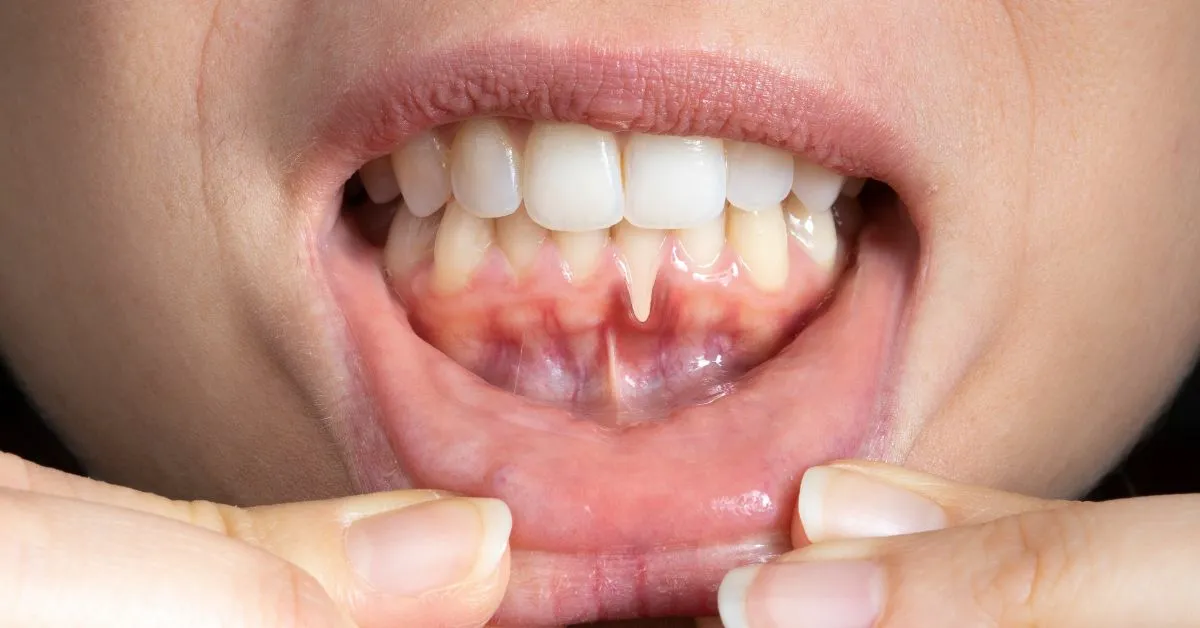

Encía retraída en un solo diente

Puede ocurrir por:

Traumatismo por cepillado

Malposición dental

Fuerzas excesivas al morder

Frenillos insertados cerca de la encía

En estos casos, el tratamiento suele ser más localizado y conservador.